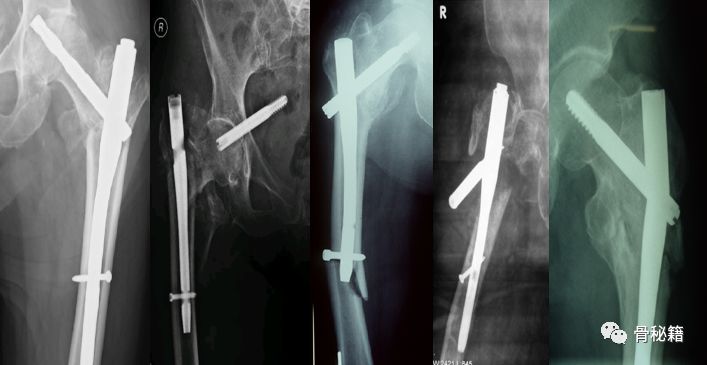

粗隆间骨折是致死率很高的手术,近年来粗隆间的并发症越来越多。

固定失败的原因有很多,医生的经验不足骨折的分类、稳定性的判定、手术经验等;内固定的选择不当内固定的选择、内固定置入等;医疗设施匮乏不同医院和地域的医生水平差别大、缺少最基本的手术配套设备。

4.这种情况下就可以在复位加压的情况下完成骨折的扩髓和固定了

5.最后再通过螺钉的加压完成最后加压

术后影像,是不是感觉不错呢??